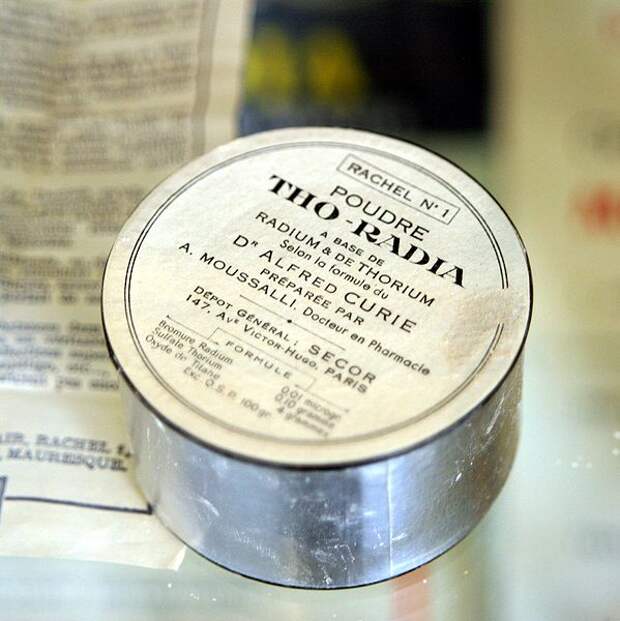

5. Радиоактивная косметика

Самым большим достоинством популярной в 1930-е годы французской косметики Flo-radia считалось содержание в ней хлористого тория и бромистого радия. Реклама косметики обещала чудеса: “Снабжает клетки жизненной силой, усиливает циркуляцию крови, делает кожу ровной, избавляет от жира, предотвращает расширение пор, избавляет от угрей, прыщиков, покраснения и пигментации, защищает, останавливает старение и разглаживает морщины, придаёт свежий и цветущий вид”.

Эта косметика вызывала у женщин бурный восторг, пока от её применения не начали отваливаться челюсти.